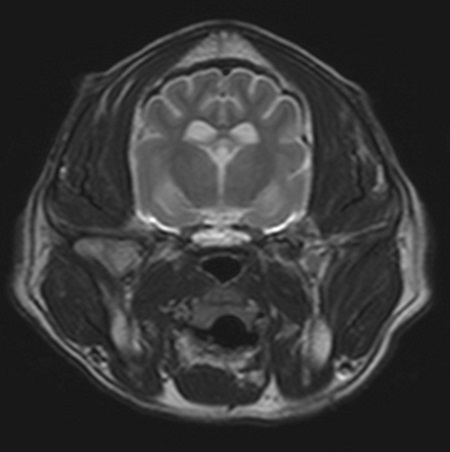

Kognitive Dysfunktionen beim alten Hund

Ältere Tiere zeigen häufig Veränderungen der kognitiven Funktionen, welche sich in veränderter Aufmerksamkeit und Reaktionen gegenüber gewohnten Reizen, Orientierungsstörungen, Änderungen des Fressverhaltens und verändertem Leistungsverhalten sowie Verlust der Stubenreinheit manifestieren können. Im englischen Sprachraum wird dieses Syndrom als „cognitive dysfunction syndrome“ (CDS) bezeichnet.

Es ist wichtig zu differenzieren, ob diese Veränderungen auf einem Alterungsprozess der Gehirnfunktionen, auf Veränderungen in der häuslichen Umgebung oder auf zugrundeliegenden pathologischen Prozessen beruhen.

Neben einer medikamentösen Behandlung und einer unterstützenden Diät werden auch allgemeine Maßnahmen empfohlen, die auf relativ einfache Weise dem alternden Hund helfen. Dazu gehört eine verlässliche, überschaubare Routine, generell die Vermeidung von großem Stress, häufigere und dafür lieber kürzere Spaziergänge, aber auch durchaus die eine oder andere geistige Anregung, wie ein Spaziergang in einer ruhigen, aber weniger bekannten Umgebung oder das Erlernen eines neuen Tricks.